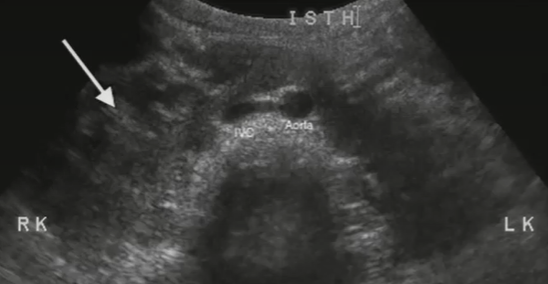

Horseshoe kidney is the ___ of the polar regions of the kidneys during fetal development. Almost always involves the ___ poles. Usually located ___ in the ___ than usual. Associated with ___ pelvis, dilated ___ that are prone to infection (pyelocaliectasis), and ___.

fusion, inferior, lower, retroperitoneum, extrarenal, calyces, stones

Fusion of the polar regions of the kidneys during fetal development. Almost always involves the inferior poles. Usually located lower in the retroperitoneum than usual. Associated with extrarenal pelvis, dilated calyces that are prone to infection (pyelocaliectasis), and stones.

Horseshoe kidney